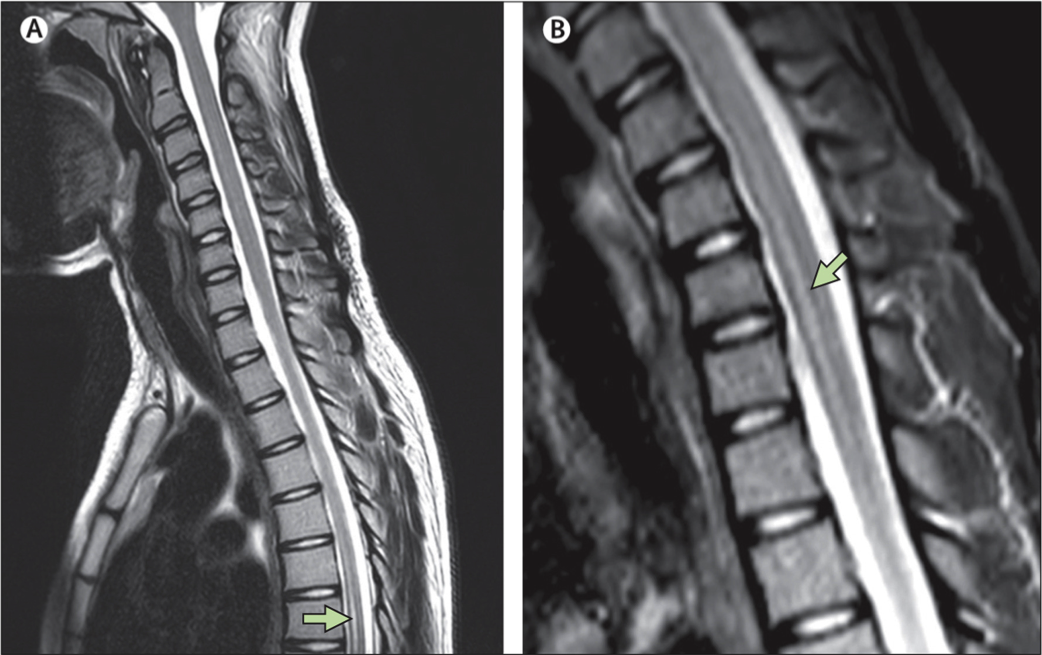

Pour connaître la raison de ces symptômes, la jeune fille a passé une batterie de tests, dont un examen d’imagerie par résonance magnétique (IRM). Ce dernier révèle « des lésions de la moelle épinière » au niveau des vertèbres cervicales et thoraciques , indiquent les auteurs.

« Un mois après son admission, elle souffrait d’une faiblesse modérée dans les jambes mais était capable de marcher sans aide. Des IRM supplémentaires ont montré une diminution l’œdème cervical », ajoutent les auteurs. A ce jour, la jeune patiente est toujours hospitalisée mais ses jours ne sont pas en danger.

Source : Acute myelitis due to Zika virus infection, The Lancet Case Report. Photo A : inflammation de

la moelle épinière au niveau thoracique. Photo B : au niveau cervical.